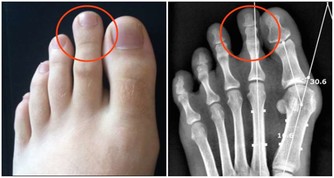

醫生一般會通過檢測前列腺特異性抗原(PSA),進而判斷前列腺是否有發生病變。

PSA是由前列腺產生的一種特殊蛋白質,男性血液中通常會含有少量的PSA。